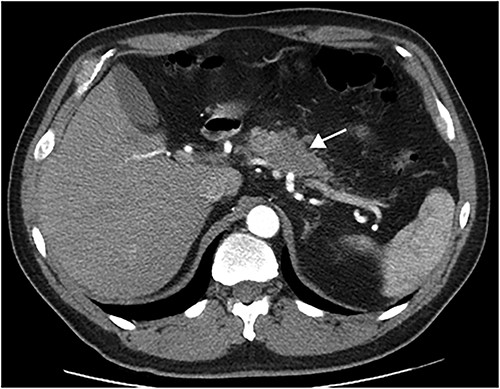

This article presents a case involving a 51-year-old male, smoker, diagnosed with a pancreatic tumor after routine exams revealed an elevated Ca19.9 tumoral marker. The CT scan shown a 4-cm hypodense pancreatic mass with poorly defined borders in the body of the pancreas (Fig. 1). The tumour had interface with vascular structures and no regional or distant metastases were observed. Consequently, surgery was recommended after Multidisciplinary Tumor Board meeting.